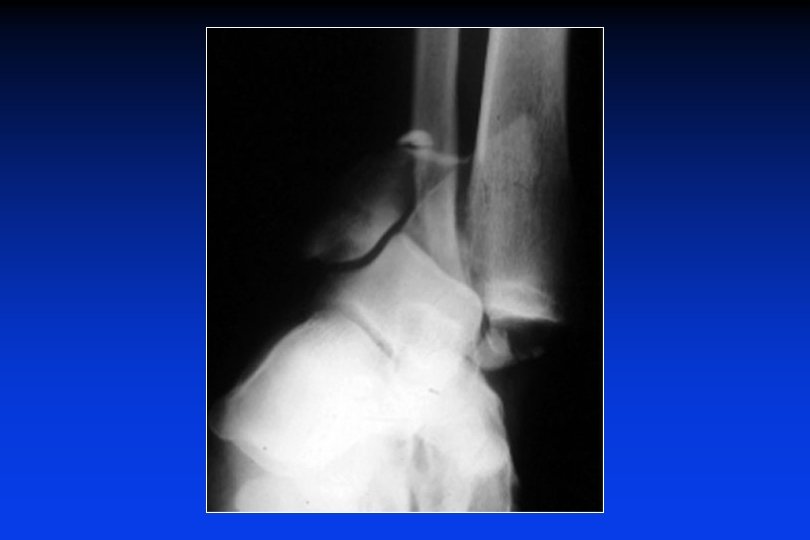

Fratture in flessione plantare Caduta dall’alto, sulla punta del piede Fratture del margine posteriore del pilone + malleoli Frattura parcellare post. Frattura marginale totale (di CUNÉO e PICOT)

Fratture in compressione • • • Fratture bi-marginali : 2 frammenti principli L’astragalo si può "lussare" verso l’avanti o verso dietro L’astragalo può impattarsi entro i due margini di frattura. Il perone é sempre fratturato La frattura del malleolo interno é sempre verticale